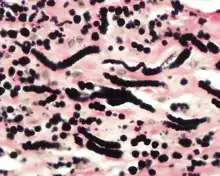

By microscopie view, there is an admixture of heavy dense bands of collagenous tissue dissected by fat and abnormal elastic fibers. The elastic fibers are often quite large and are easily identified. The elastic fibers are coarse, thick, and darkly eosinophilic, often fragmented into globules, creating a "string of pearls" or "pipe cleaner" appearance. Because of degeneration, the elastic fibers will appear as globules with a serrated or "prickled" edge.[4]

The elastic fibers will be highlighted by a Weigert or von Gieson elastic stains.[9]